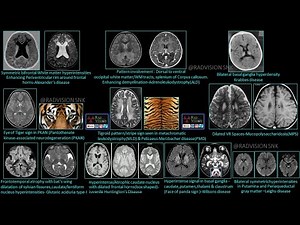

- Neuroradiology